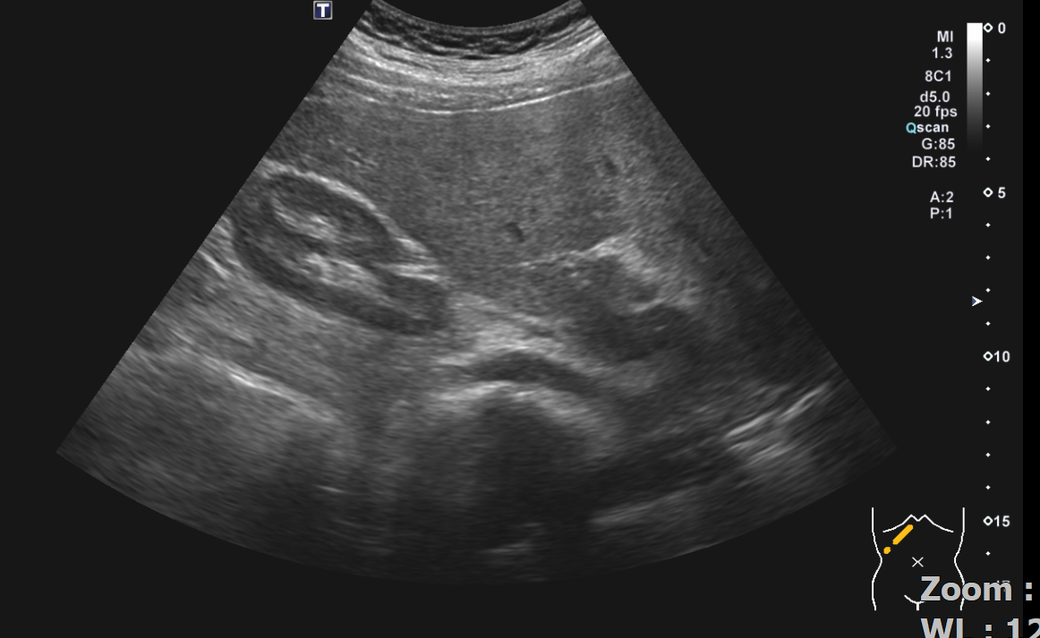

복부초음파 신장 물혹 보이나요? 사진올려봐요

신장물혹 0.6cm mri에는 나오는데 복부초음파에는 소견이없어서요

• 1번 째 사진

올려주신 사진 중 우측 신장이 찍힌 영상은 한 장이며 단면 영상만으로는 물혹 유무를 확인할 수 없습니다.